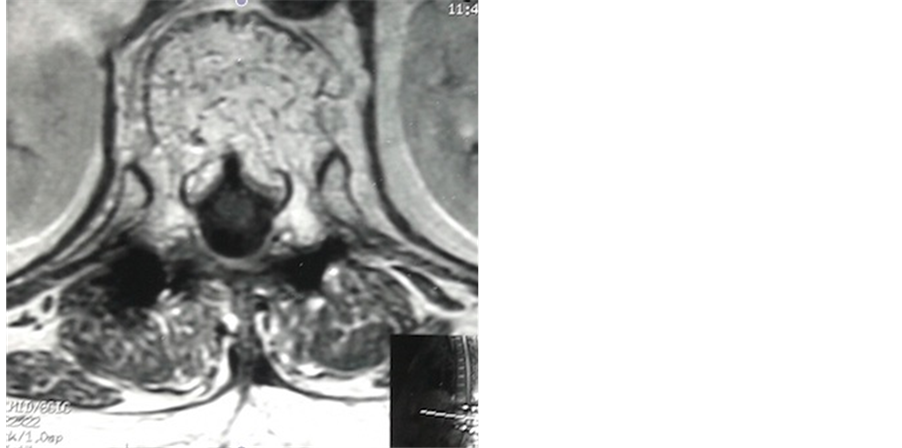

Plain radiographs of the thoracolumbar spine showed L1 and L2 benign vertebral fractures with grid appear- ance at T12 vertebra (Figure 1). MRI revealed T12 intensity signal on T1 and T2 with ductal extension, com- patible with aggressive vertebral angioma (Figure 2 and Figure 3).

Figure 3. Axial MRI T12 image depicted that the lesion involved the vertebral body and spread into spinal canal.